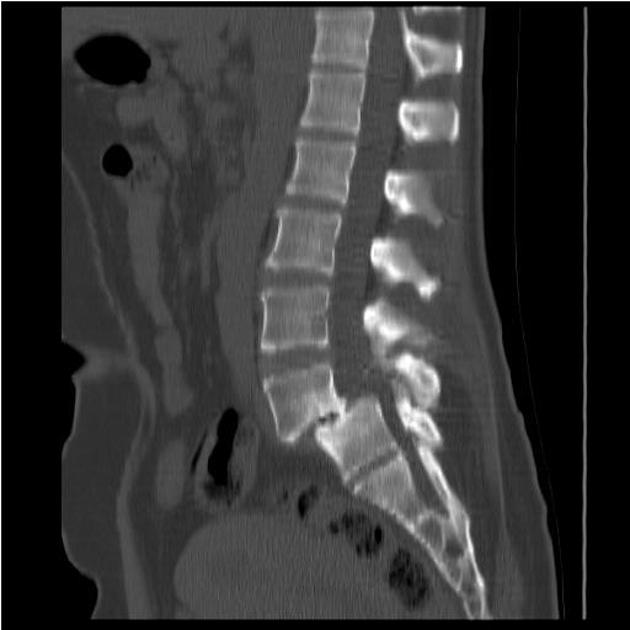

В основе диагностического обследования пациентов с признаками смещения позвонков лежат лучевые методы лабораторной диагностики. Первоначально проводится стандартная процедура спондилографии в вертикальном осевом положении позвоночника.

Следующий этап диагностического осмотра – это уточнение степенной фазы редукции смещенного тела позвонка. С этой целью под крестцовый отдел позвоночника подкладывают жесткий валик и после выдержки в 10-15 минут проводят спондилографию в боковой сагиттальной проекции.

Более информативную картину диагностического исследования по характеру смещения позвонка и его мобильности можно получить при саккорадикулографии, магнитно-резонансной и компьютерной томографии.